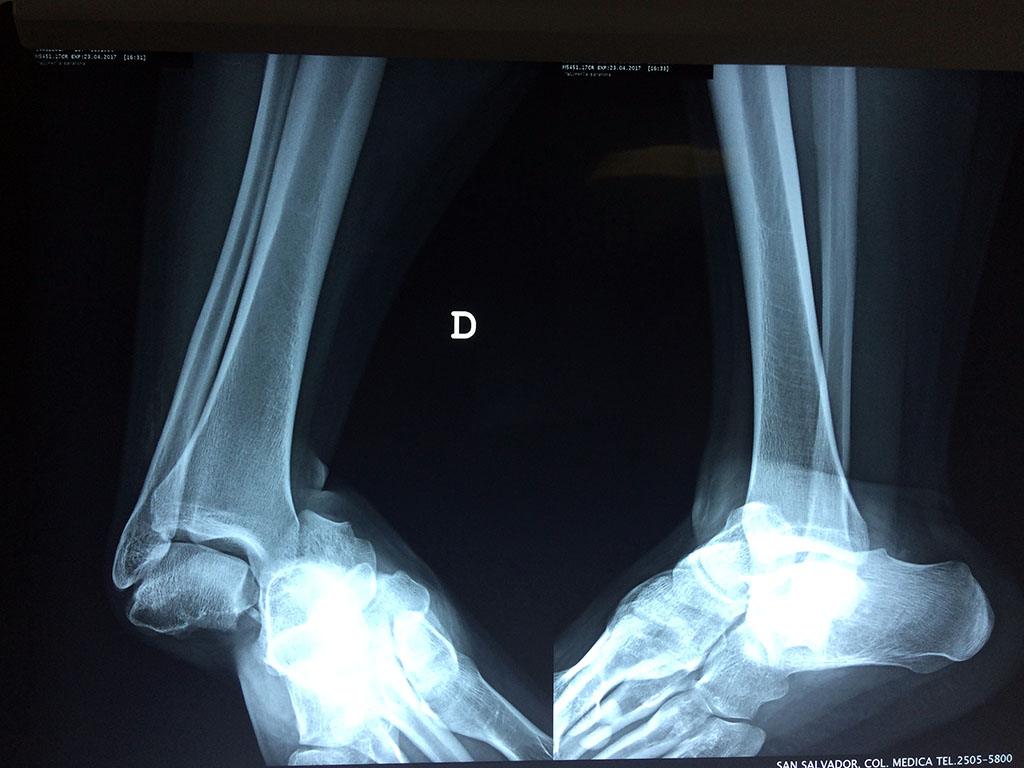

Una fractura de tobillo es la rotura de uno o más de los huesos del tobillo. Estas fracturas pueden ser:

- Producirse en uno o ambos lados del tobillo.

- Los extremos de los huesos están desalineados entre sí (desplazados).

- La fractura se extiende hasta la articulación del tobillo (fractura intra-articular).